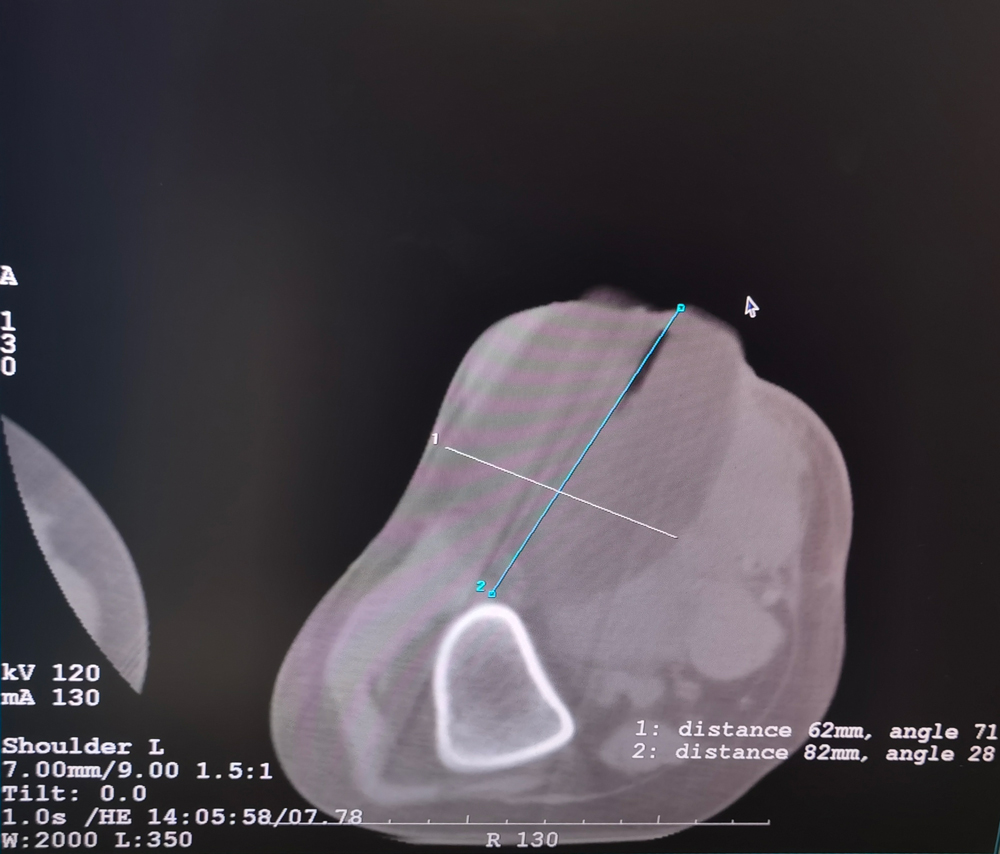

女,42歲,復(fù)發(fā)性脂肪瘤,病灶位于右側(cè)膝關(guān)節(jié),直徑大小13cm。采用雙針方案,共進行6個凍融循環(huán),最大冰球直徑達8.2cm,術(shù)中多方位治療全面覆蓋病灶范圍。患者術(shù)后狀況良好。